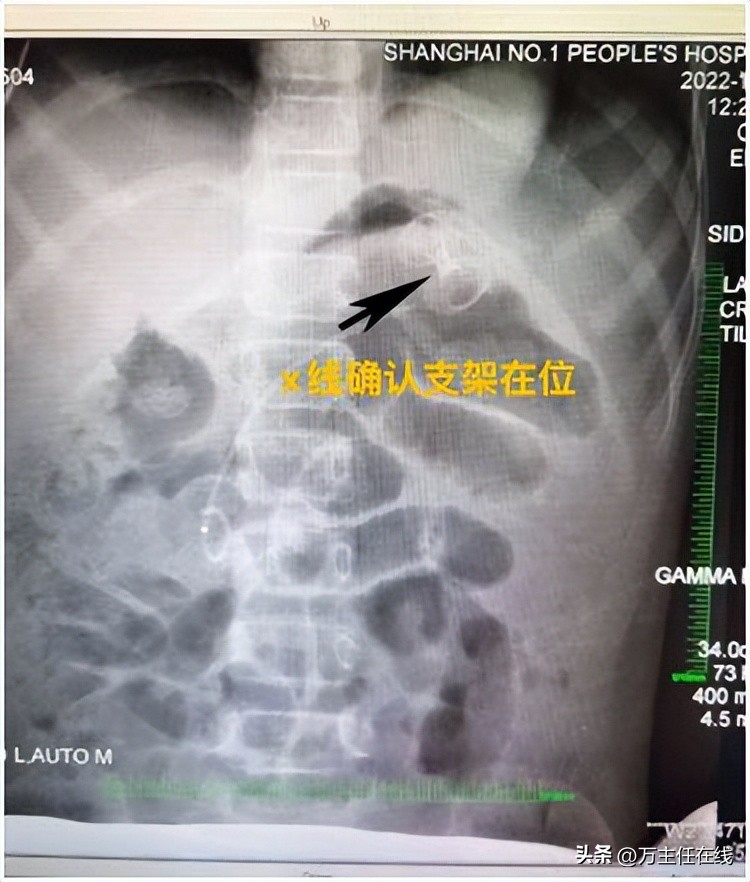

▲ 成功置入AXIOS电切引流一体式支架

手术当日,手术团队先以超声内镜精确定位胰腺尾部约12厘米大小的囊性病灶,用19G穿刺针避开主要血管后穿刺。随着穿刺针刺入,大量棕褐色浑浊囊液涌出,这正是造成患者反复感染的根源。在迅速以X线定位后,手术团队采用新型的“AXIOS电切引流一体式支架”进行后续操作,以减少术中器械交换、降低内瘘及出血风险的同时进行高效引流。万荣教授精准操作内镜及附件逐层切开胃粘膜、囊壁,将支架送入囊腔内。由于患者年幼,胃腔狭小,操作空间十分有限。万荣教授反复尝试最合适的释放位置,最终将支架头端以较特殊的“胃底朝向位”确认后释放。放置完成后,可见胃内金属支架在位、囊液引流通畅。在麻醉科和护理团队的共同努力下,手术用时不到1小时即告完成。